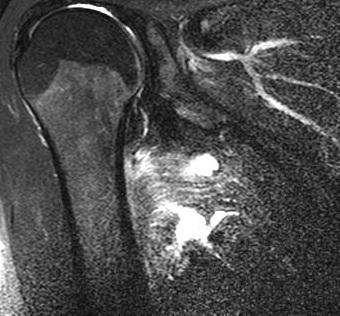

MRI(T2 FS) : 대흉근 파열(Pectoralis major rupture)

MRI를 통해 부분파열과 완전파열, 급성 손상과 만성 손상의 구별이 가능합니다.